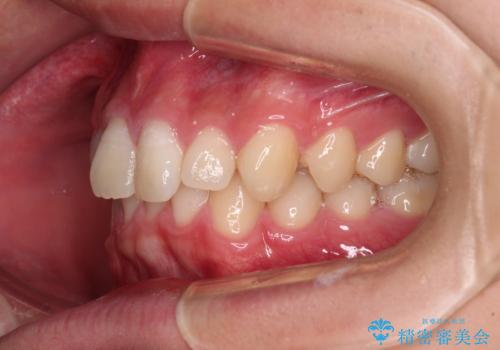

- 上下前歯のデコボコと深い咬み合わせを気にして来院された患者様です。

下顎前歯が一本欠損しており、下顎の歯列が小さいため、ディープバイトになりやすい状態でした。

傾斜しいている大臼歯を立ち上げながら、下顎歯列を上顎に対して前方位となるように工夫し、デコボコを解消した上でディープバイトも改善することができました。